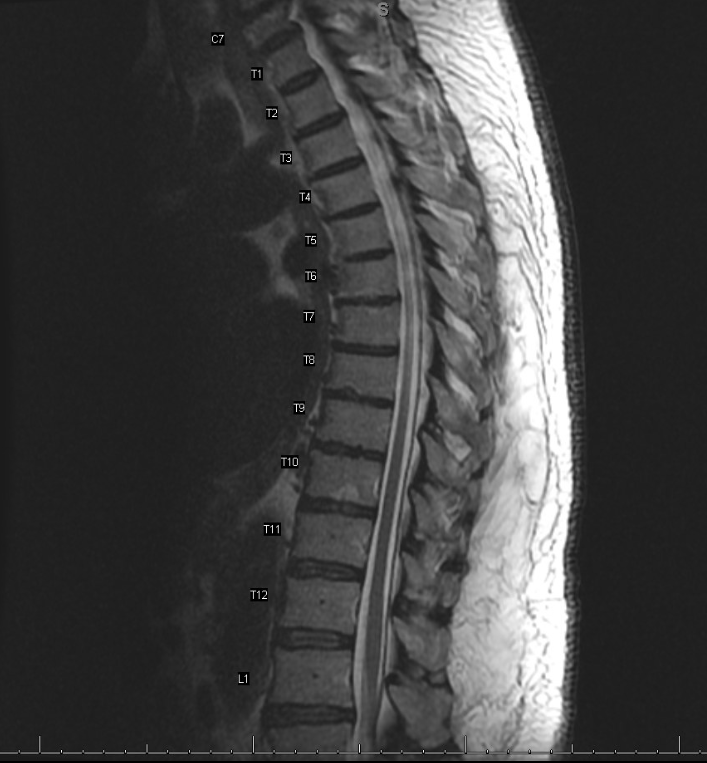

Case Presentation: A 73 year old male with a history of hypertension and osteoarthritis presented to the hospital with progressively worsening back pain. He has chronic back pain, but suddenly woke up and noticed a difficult time walking and standing, resulting in a fall. His symptoms were associated with subjective fevers, chills, and diaphoresis. Vital signs revealed high grade fever, tachycardia, tachypnea, and hypotension. Laboratory findings revealed leukocytosis and lactate elevation. He received intravenous hydration, empiric antibiotics, and an infectious workup was started. Urinalysis, chest radiograph, CT abdomen, pelvis, and CT spine were negative for any acute or infectious process. Blood cultures grew pan-susceptible Proteus mirabilis. Antibiotics were de-escalated to Ceftriaxone. Given his persistent back pain, MRI of his spine was obtained which revealed L5-S1 and T10-T11 endplate enhancement suggesting multifocal early discitis and osteomyelitis. Blood cultures cleared after three days of Ceftriaxone and he remained afebrile. The patient was discharged with plans to complete 6 weeks of antibiotic therapy.